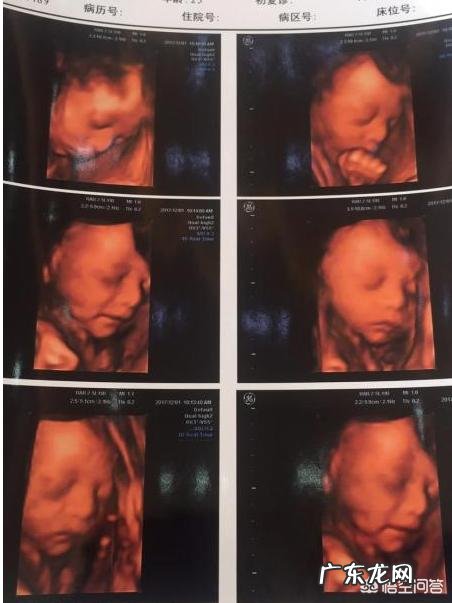

怀孕5个半月,也就是孕22周,此时胎儿的不仅会笑,还会哭、会打嗝 。他在子宫里无忧无虑,所以动作和表情都相对轻松,胎动也会比较多 。

22周已经可以做四维排畸检查了(建议22周~26周),如果宝宝比较配合,可以看到他笑的样子并且拍下来做纪念 。上面这张图就是一位粉丝妈妈提供的,最后一副是宝宝笑的样子 。

总之,5个半月的胎儿已经可以有面部表情了,比如微笑、不开心、撇嘴等,不过这些需要通过B超检查才能看到,妈妈们可以在做四维的时候留个照片或者DV做纪念,说不定你家宝宝也在笑呢!

怀孕5个半月,胎儿已经有了面部表情,喜怒哀乐都会有,当然胎儿也会发笑 。

5个半月的胎儿相当于22周,眼睛、鼻子、眉毛、耳朵、嘴巴等五官面貌结构完整,有面部表情可以轻松观察到 。

在做四维彩超的时候很容易捕捉到胎儿的微笑,这时不要觉得奇怪,这是胎儿正常的生理反应 。